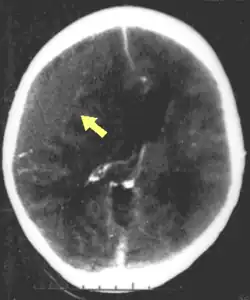

Hematomas, also focal lesions, are collections of blood in or around the brain that can result from hemorrhage.[11] Intracerebral hemorrhage, with bleeding in the brain tissue itself, is an intra-axial lesion. Extra-axial lesions include epidural hematoma, subdural hematoma, subarachnoid hemorrhage, and intraventricular hemorrhage.[38] Epidural hematoma involves bleeding into the area between the skull and the dura mater, the outermost of the three membranes surrounding the brain.[11] In subdural hematoma, bleeding occurs between the dura and the arachnoid mater.[23] Subarachnoid hemorrhage involves bleeding into the space between the arachnoid membrane and the pia mater.[23] Intraventricular hemorrhage occurs when there is bleeding in the ventricles.[38]

Traumatic brain injury may cause a range of serious coincidental complications that include cardiac arrhythmias[118] and neurogenic pulmonary edema.[119] These conditions must be adequately treated and stabilised as part of the core care. Surgery can be performed on mass lesions or to eliminate objects that have penetrated the brain. Mass lesions such as contusions or hematomas causing a significant mass effect (shift of intracranial structures) are considered emergencies and are removed surgically.[23] For intracranial hematomas, the collected blood may be removed using suction or forceps or it may be floated off with water.[23] Surgeons look for hemorrhaging blood vessels and seek to control bleeding.[23] In penetrating brain injury, damaged tissue is surgically debrided, and craniotomy may be needed.[23] Craniotomy, in which part of the skull is removed, may be needed to remove pieces of fractured skull or objects embedded in the brain.[120] Decompressive craniectomy (DC) is performed routinely in the very short period following TBI during operations to treat hematomas; part of the skull is removed temporarily (primary DC).[121] DC performed hours or days after TBI in order to control persistently high intracranial pressures (secondary DC), although can reduce intracranial pressure and length of stay in ICU, but have worse Glasgow Coma Scale (GCS) scores, and high chances of death, vegetative state, or severe disability when compared to those receiving standard medical therapies.[122][123][10][121]